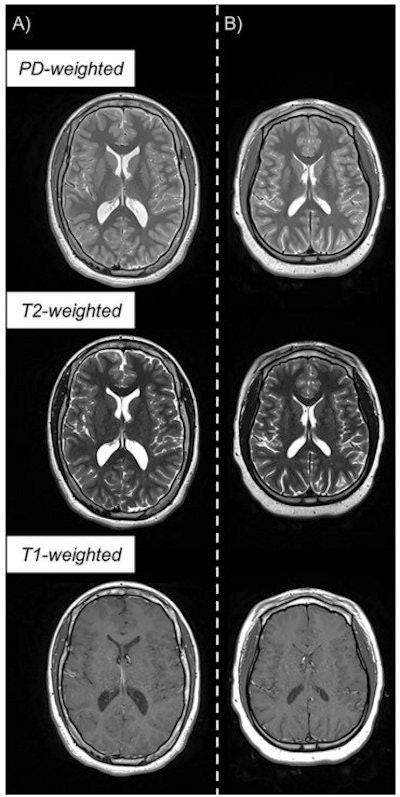

For this current research, McNaughton's group used quantitative MRI to assess the brains of adolescents born preterm. The project included MRI data from 368 ELGAN-ECHO adolescents ages 14 to 16; of the total study cohort, 252 of the children developed neurotypically and 116 developed atypically. The investigators compared MRI results such as brain volume and proton density between the two cohorts and between boys and girls.

"Quantitative MRI in a large dataset allows you to identify small differences between populations that may reflect microstructural tissue abnormalities not visually observable from imaging," Jara said in the RSNA statement.

Those adolescents who had atypical neurological development showed this on quantitative MRI, with "subtle differences in white matter related to proton density that corresponded with less free water," the researchers noted. (Lower white-matter values are associated with atypical neurological development.)